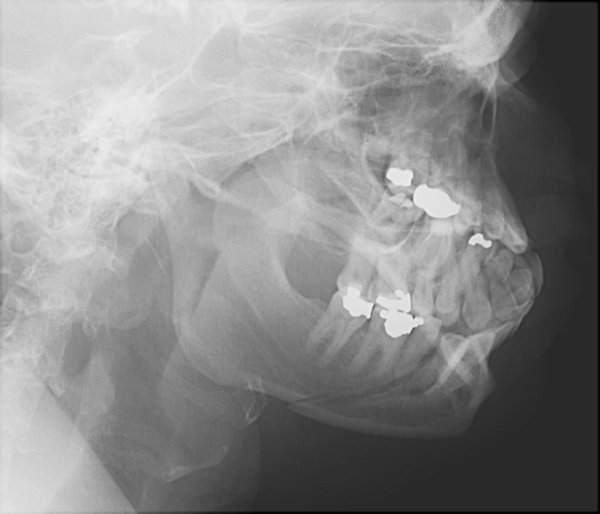

Return to Mandible Fracture